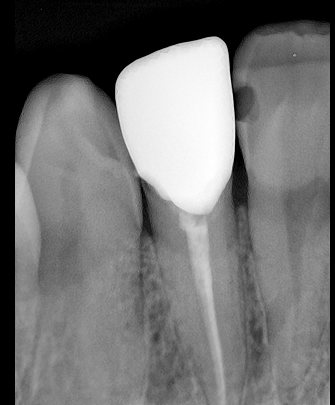

CR/DR 牙齿分割阶段记录

当前进展

- 完成了 CR/DR 牙齿相关分割训练

相关测试

遇到的问题

- 训练过程中出现过 mask 下移问题

- 部分结果会出现 box 填充异常

- mask 边缘仍然有比较明显的锯齿感

参考